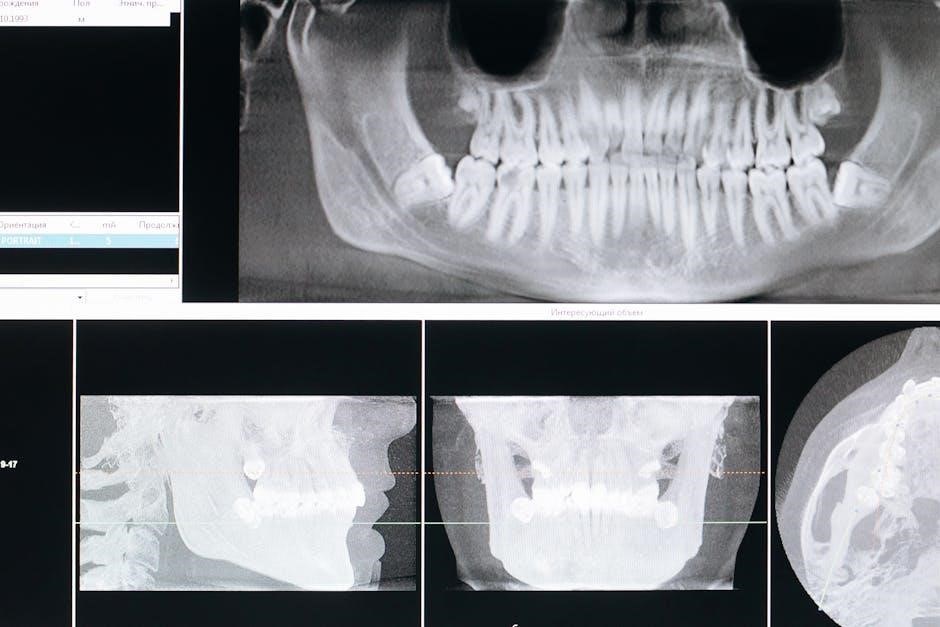

Radiographic Bone Loss Assessment

Radiographic bone loss complements attachment loss evaluation in staging periodontitis, offering a visual representation of alveolar bone destruction․ The 2018 classification recognizes its importance, advocating for standardized radiographic techniques for accurate assessment․ Percentage of bone loss relative to tooth length is a key metric, aiding in differentiating stages․

Horizontal and vertical bone loss patterns are also considered, influencing staging decisions․ While attachment loss reflects past destruction, radiographic analysis reveals current bone levels․ This combined approach provides a comprehensive understanding of disease severity․ It’s crucial to note that radiographs should be interpreted alongside clinical findings, as they don’t always perfectly correlate with attachment levels․ Accurate radiographic interpretation is vital for effective treatment planning and monitoring disease progression․